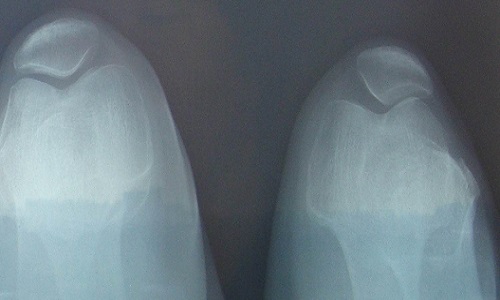

患者完全没有症状,未意识到有杵状指。在出现杵状指之前即有明显的慢性骨骼疼痛,以酸痛为主,部位较深,常不能明确指出具体部位,无法坚持工作。杵状指为最突出的临床表现之一,指(趾)端呈球状正常的甲周160度角度减小,手指在甲床基部厚度超过远端指间关节的厚度,甲床基部周径大于远端指间关节的周径。由于甲床软组织增生和水肿,指甲触诊有一种“摆动感”。晚期皮肤增厚,指甲变弯,发绀,产生鼓槌样畸形。部分患者手足增粗变厚,长度不增加而呈铲状或兽掌状。

有杵状指(趾)、恶性突眼及胫前黏液性水肿,X线检查示掌骨骨膜下新骨形成,多发于甲亢治疗引起甲状腺功能减低时。有明显的甲亢病史,可资鉴别。